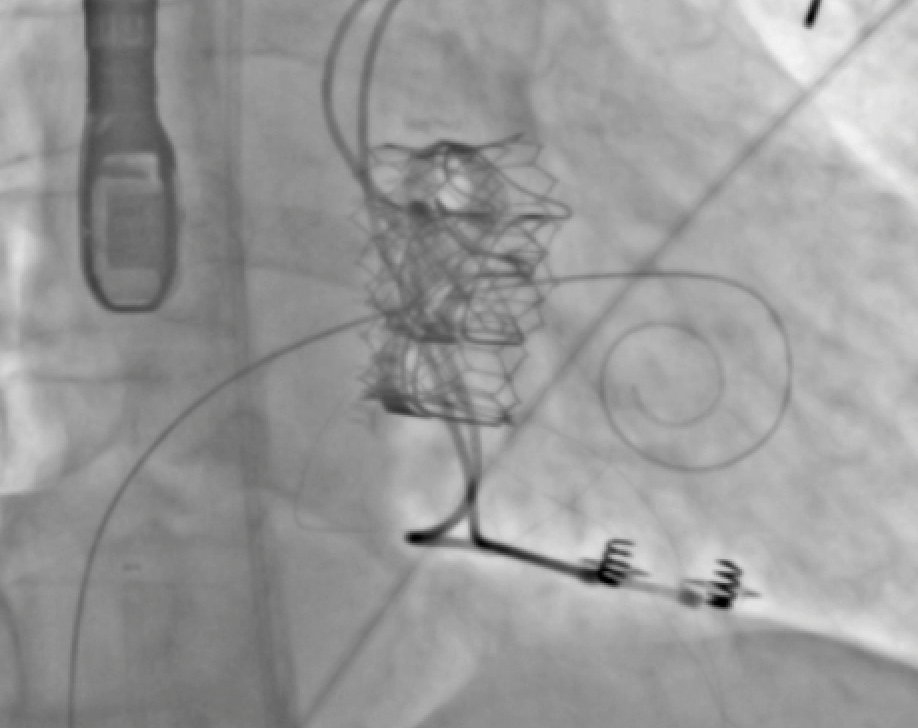

Mitraclip in patient with prior 35mm ASO TSP planning with CT Baylis superior/post to device-> Septostomy (7mm)-> Clip for success! This will be a more frequent hurdle for SHD... any other strategies? #mitraclip #ASD @SHYoonMD @PWengrofskyMD @ryankaple